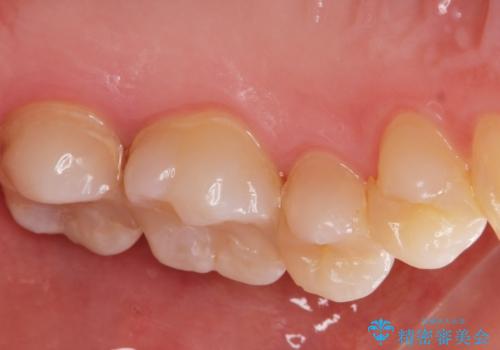

- 矯正前の患者様です。検査をしたところ虫歯が見られたので拡大鏡下で虫歯を取り除き

e-maxインレーで治療を行いました。

虫歯が多数ありましたのでまずは2本虫歯治療を行いました。

適合の良い詰め物が入りました。